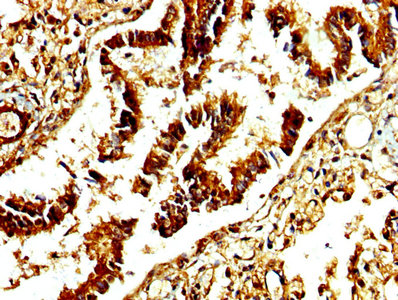

Immunohistochemistry of paraffin-embedded human heart tissue using CSB-PA001311LA01HU at dilution of 1:100

Immunohistochemistry of paraffin-embedded human liver tissue using CSB-PA001311LA01HU at dilution of 1:100

IHC image of CSB-PA001311LA01HU diluted at 1:250 and staining in paraffin-embedded human lung tissue performed on a Leica BondTM system. After dewaxing and hydration, antigen retrieval was mediated by high pressure in a citrate buffer (pH 6.0). Section was blocked with 10% normal goat serum 30min at RT. Then primary antibody (1% BSA) was incubated at 4°C overnight. The primary is detected by a biotinylated secondary antibody and visualized using an HRP conjugated SP system.